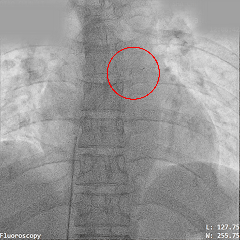

释放氧化膜封堵器左右盘面

牵拉试验封堵器稳定

释放封堵器

封堵器稳固夹持